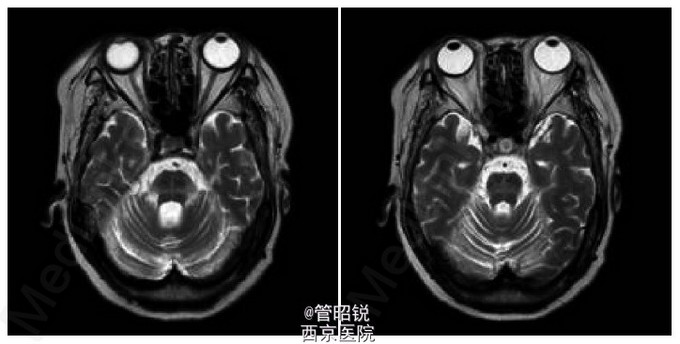

患者,女,71岁。有高血压和非胰岛素依赖型糖尿病病史。以突发的眩晕和共济失调入院。入院时血压146/98mmHg,心率97次/分,节律整齐。神经系统查体,神志清,除构音障碍外,无明显异常。小脑功能测试显示严重的共济失调,站立时需要扶持。双侧肱二头肌和膝反射减弱。巴彬斯基征阳性。T2WI 弥散加权显示双侧脑桥和右侧小脑急性腔梗。MRA显示严重的双侧椎动脉闭塞。给予口服阿司匹林治疗。三天后,病情进展为左眼外侧凝视受限和水平性复视。再次进行了检查,显示右侧脑桥正中旁的新发小的急性腔梗。静脉给予肝素治疗5天后,症状逐渐改善,但共济失调仍存在。转入康复医院1年后,眩晕减轻,可以扶拐行走。随访的T2WI显示橄榄脑桥小脑萎缩和脑桥十字征。